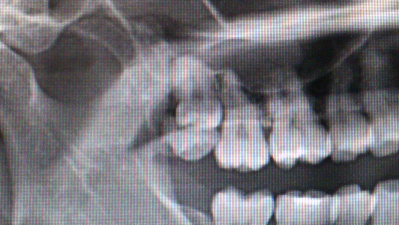

通常歯は8番目までしかありませんが、9番がある方でした。

よくみると2つありますね。

両方とも歯茎に埋まっていました。